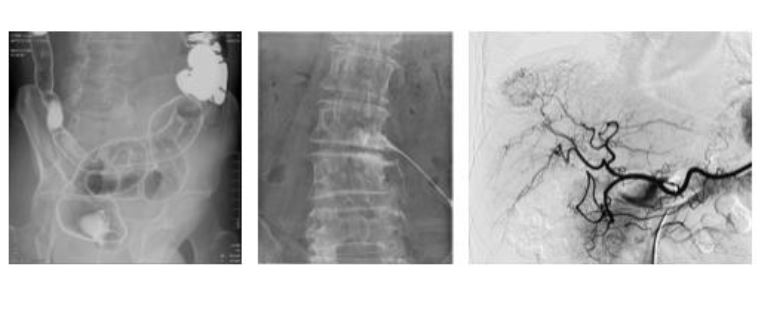

Sonialvision G4

Uniwersalny aparat R/F typu telekomando do cyfrowej radiografii i fluoroskopii Sonialvision G4 z płaskim panelem detekcyjnym i z cyfrowym systemem obróbki obrazu firmy SHIMADZU

Uniwersalny aparat R/F typu telekomando do cyfrowej radiografii i fluoroskopii Sonialvision G4 z płaskim panelem detekcyjnym i z cyfrowym systemem obróbki obrazu firmy SHIMADZU.

• Płaski Detektor Obrazowy (Flat Panel Detector)

• System cyfrowej obróbki obrazu badań rtg

• Unikalne oprogramowanie ,,Slot Radiography” do projekcji kończyn długich, kręgosłupa lub całego ciała

• Oprogramowanie do tomosyntezy - Oprogramowanie umożliwia uzyskiwanie i przeglądanie cyfrowych obrazów z szybkiej planigrafii cyfrowej (tomosyntezy) u pacjentów leżących, jak również stojących.

• Pakiet DSA do badań naczyniowych